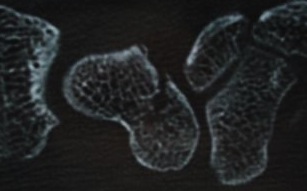

Versorgung eines Kahnbeinbruches mit einer Titanschraube, die im Knochen versenkt wird.

Ausheilung des Bruches